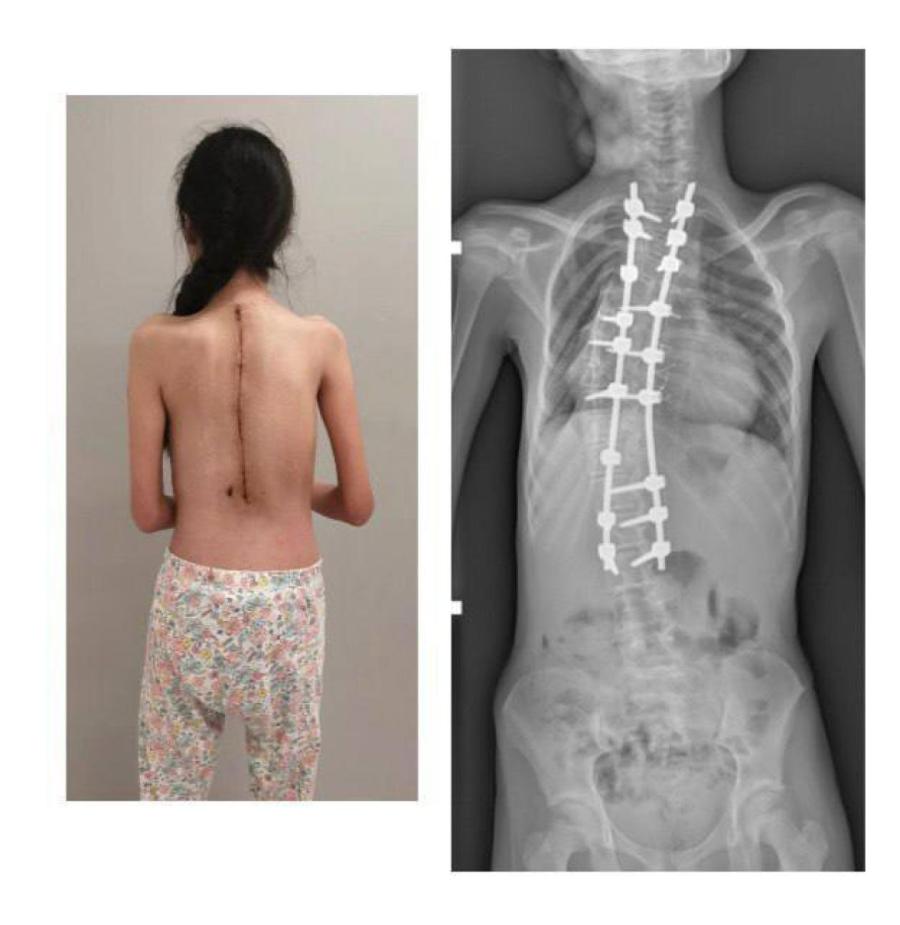

Хирурги Российской детской клинической больницы установили девочке транспедикулярные винты, которые впоследствии соединили между собой стержнями. Затем постепенно изменили ось позвоночника. После этого уложили костный аутотрансплантат, чтобы обеспечить ее максимальную стабильность в будущем.

Теперь реберный горб полностью устранен. Операция улучшила функцию органов грудной клетки. Сейчас девочка восстановилась и вернулась к активному образу жизни.